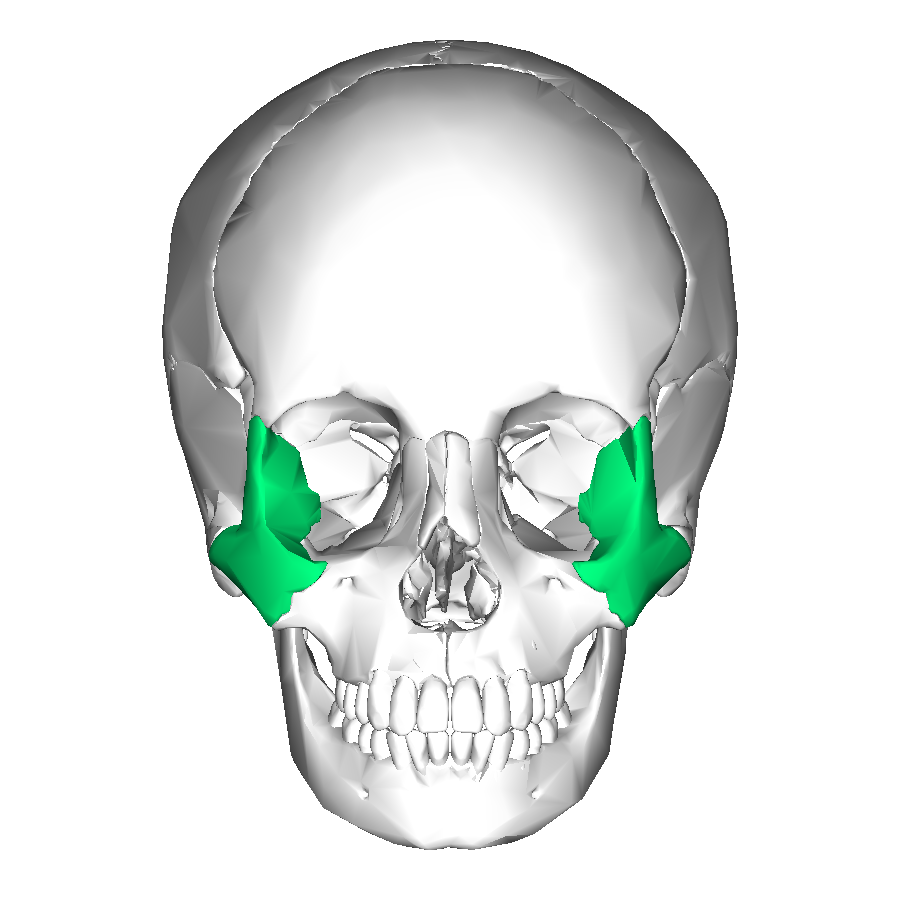

What is this region?

Zygomatic Bone